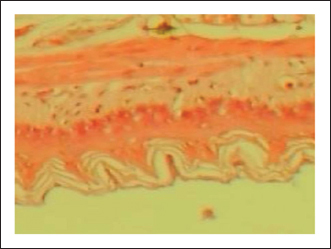

The gastric tissue slides were examined under a microscope for morphological changes such as hyperemia, hemorrhage, edema, necrosis, inflammatory changes, distortion, erosion, and ulcers caused by the destructive effects of indomethacin on stomach tissues. No pathological changes were observed in the normal control group (Fig. 1). Rats in the ulcer control group showed significant damage to the surface epithelium, necrotic areas penetrating the mucosal layer, and severe edema of the submucosal layer. Additionally, there was congestion with infiltration of inflammatory cells (Fig. 2). Histological results revealed that the treated rats with ranitidine had less protection of the gastric lining due to mild infiltration of leucocyte and edema in the submucosal layer, in addition to less disruption in both the superficial and deep mucosal layers. Treatment doses (300, 400 and 500 mg/kg) with P. farcta extract. Groups treated with P. farcta extract (300 and 400 mg/ kg) showed mild infiltration of inflammatory cells, edema, or significant disruption of the deep mucosa (Figs 5 and 6) while, P. farcta extract group (500mg/ kg) prevented histological changes and showed no infiltration of inflammatory cells, edema, or significant disruption of the deep mucosa (Figs 3, 4 and 7).

Fig. 2. Normal control group received distilled water, No pathological changes were observed.

Fig. 7. Prosopis farcta extract (500 mg/kg) prevented histological changes, nofiltration of inflammatory cells, edema, or distruption of deepmucosa.